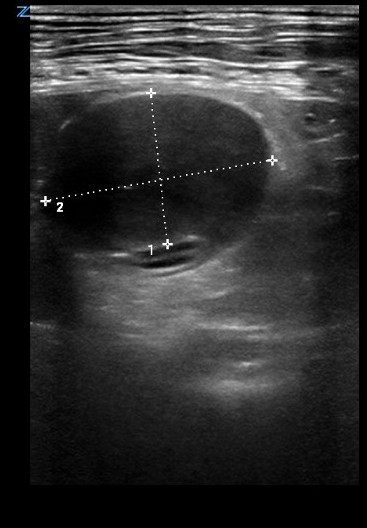

La ecografía abdominal (Resona7, Mindray, Shenzhen, China) evidenció una estructura de 4 cm de aspecto hipoecoico y bordes redondeados adherida a la capa serosa del duodeno, sin captación de señal Doppler. Los diagnósticos diferenciales compatibles con esta lesión son la neoplasia intestinal, el hematoma intramural intestinal o la presencia de un granuloma (Fig. 3 y Vídeo 1).

Los hallazgos laboratoriales suelen ser inespecíficos. El diagnóstico presuntivo suele llevarse a cabo mediante técnicas de diagnóstico por imagen como la ecografía y la radiografía con contraste, ya que el diagnóstico definitivo es histopatológico. Aunque en medicina veterinaria estas técnicas aún no han sido descritas, en medicina humana se utilizan pruebas de imagen avanzadas como son la resonancia magnética o la tomografía computarizada.[ Moore R, Carpenter J: Intramural intestinal hematoma causing obstruction in three dogs. J Am Vet Med Assoc. 1984; 184(2): 186-188. [PubMed] , Hsu TC, Lin LS, Chung CS, et al: Colonic Intramural Hematoma in a Cat: A Case Report. Front Vet Sci. 2022; 9: 913862. [PubMed] ]